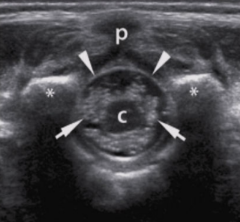

p

spinous processes

arrowheads

arachnoid/dural layer

e

epidural space

*

subarachnoid space w/ CSF

sc

hypoechoic spinal cord